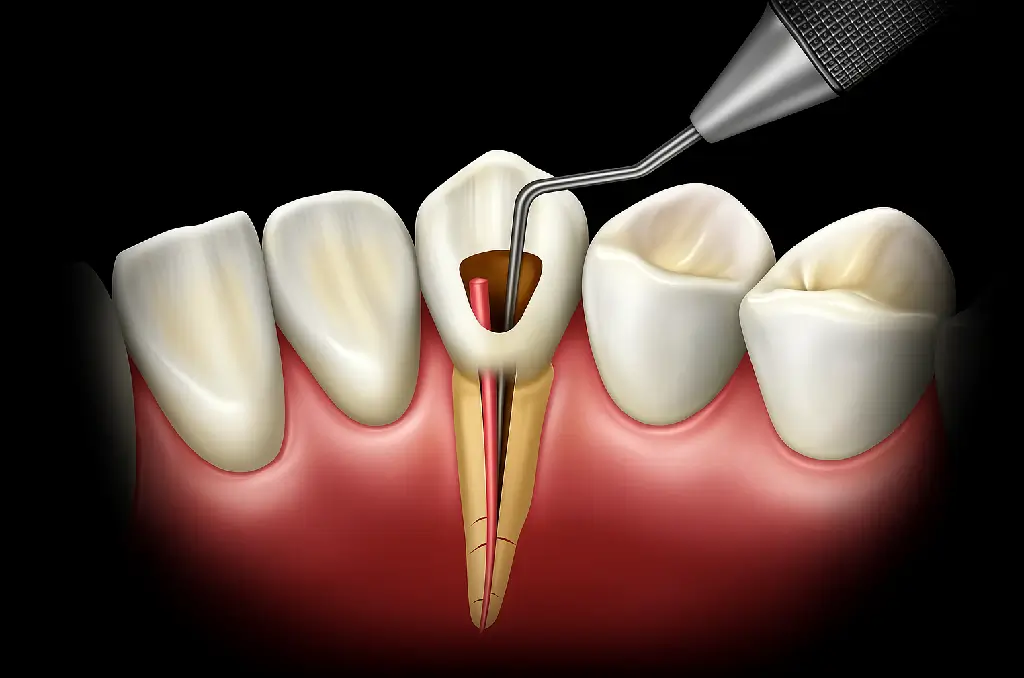

Diş İmplantı Tedavisi Estetik Diş Hekimliği Çene Cerrahisi Pedodonti (Çocuk Diş Hekimliği) Kanal Tedavisi (Endodonti) Ortodonti Periodontoloji Organik Diş Dolgusu Holistik Diş Hekimliği Klinik Bilgilerimiz Telefon: +90 212 227 2084 E-Posta: mail@dentcorner.com Adres: Beşiktaş Caddesi, Deniz Yıldızı İş Merkezi, No:1 Kat 3 Pk: 34353 Beşiktaş-İstanbul Holistik Diş Hekimliği: Sağlığın Bütünsel Yansıması Holistik diş hekimliği, ağız